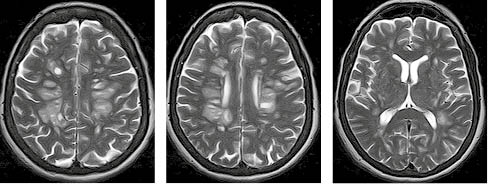

Завдяки виконаному МРТ-дослідженню головного мозку візуалізувано множинні вогнища, переважно овоїдної та округлої форм, розташовані в глибокій білій речовині обох семіовальних центрів. Вогнища гіперінтенсивні в режимах Т2/Flair і Т2, поліморфні. Типовою клінічною ознакою, характерною для перебігу ГРЕМ, на відміну від РС, є те, що більшість запальних вогнищ накопичують контраст. На зображеннях у режимі Т2 GRE не виявлено даних, які б могли свідчити про крововиливи в структурі вогнищ. МРТ-зображення головного мозку пацієнта в різних режимах, представлені на рисунках 6-9, підтверджують діагноз ГРЕМ.

Підписатися/images/nn257-1622023r6_.jpg)

/images/nn257-1622023r7_.jpg)

/images/nn257-1622023r8_.jpg)

/images/nn257-1622023r9_.jpg)